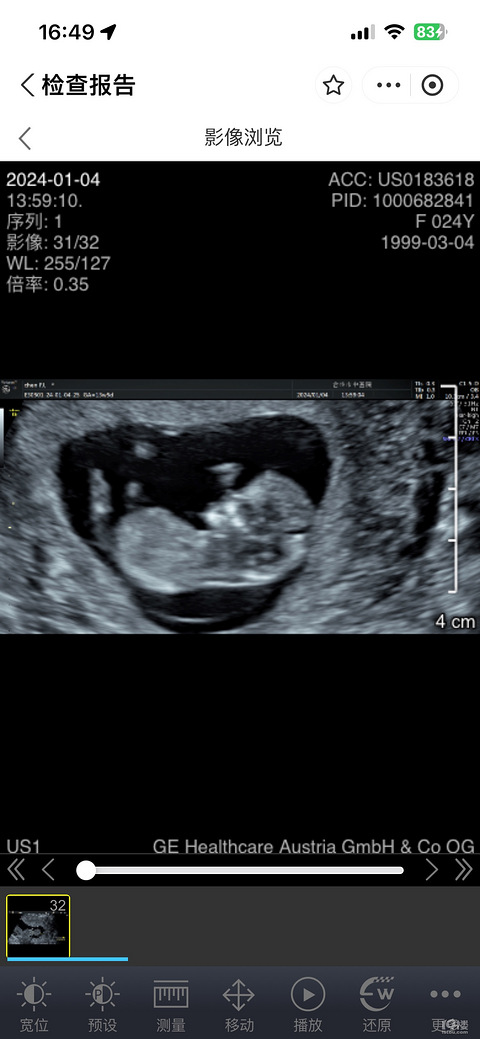

预产期:2024.1.20建卡医院:台州妇女儿童医院产检医院:台州妇女儿童医院计划生产医院:台州妇女儿童医院 好孕分享:生理期推迟了十几天天,抱着不可置信的心态买了验孕棒,终于在有一天早晨,惊喜的看到了代表宝宝孕育的两条杠。B超照片: